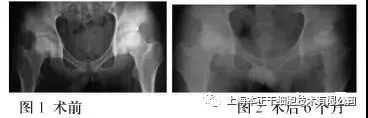

由上海某三甲医院2012-2014年开展的,间充质干细胞(MSC)治疗股骨头缺血性坏死的临床试验中,收治患者20人。治疗前后髋关节Harris疼痛评分比较(下图)

按Harris疼痛评分,满分44分。与治疗前疼痛均数积分比较,治疗后治疗组增加18.46分。对照组增加16.80分;结果随访6-30个月,两组病例治疗后髋关节疼痛均获得明显减轻。

X射线骨形态变化改善及MRI股骨头坏死区体积变小可认联合治疗有效。